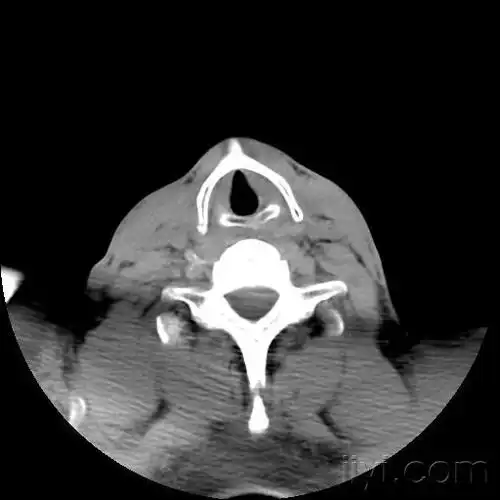

甲状软骨(常见病变,少见部位),请欣赏